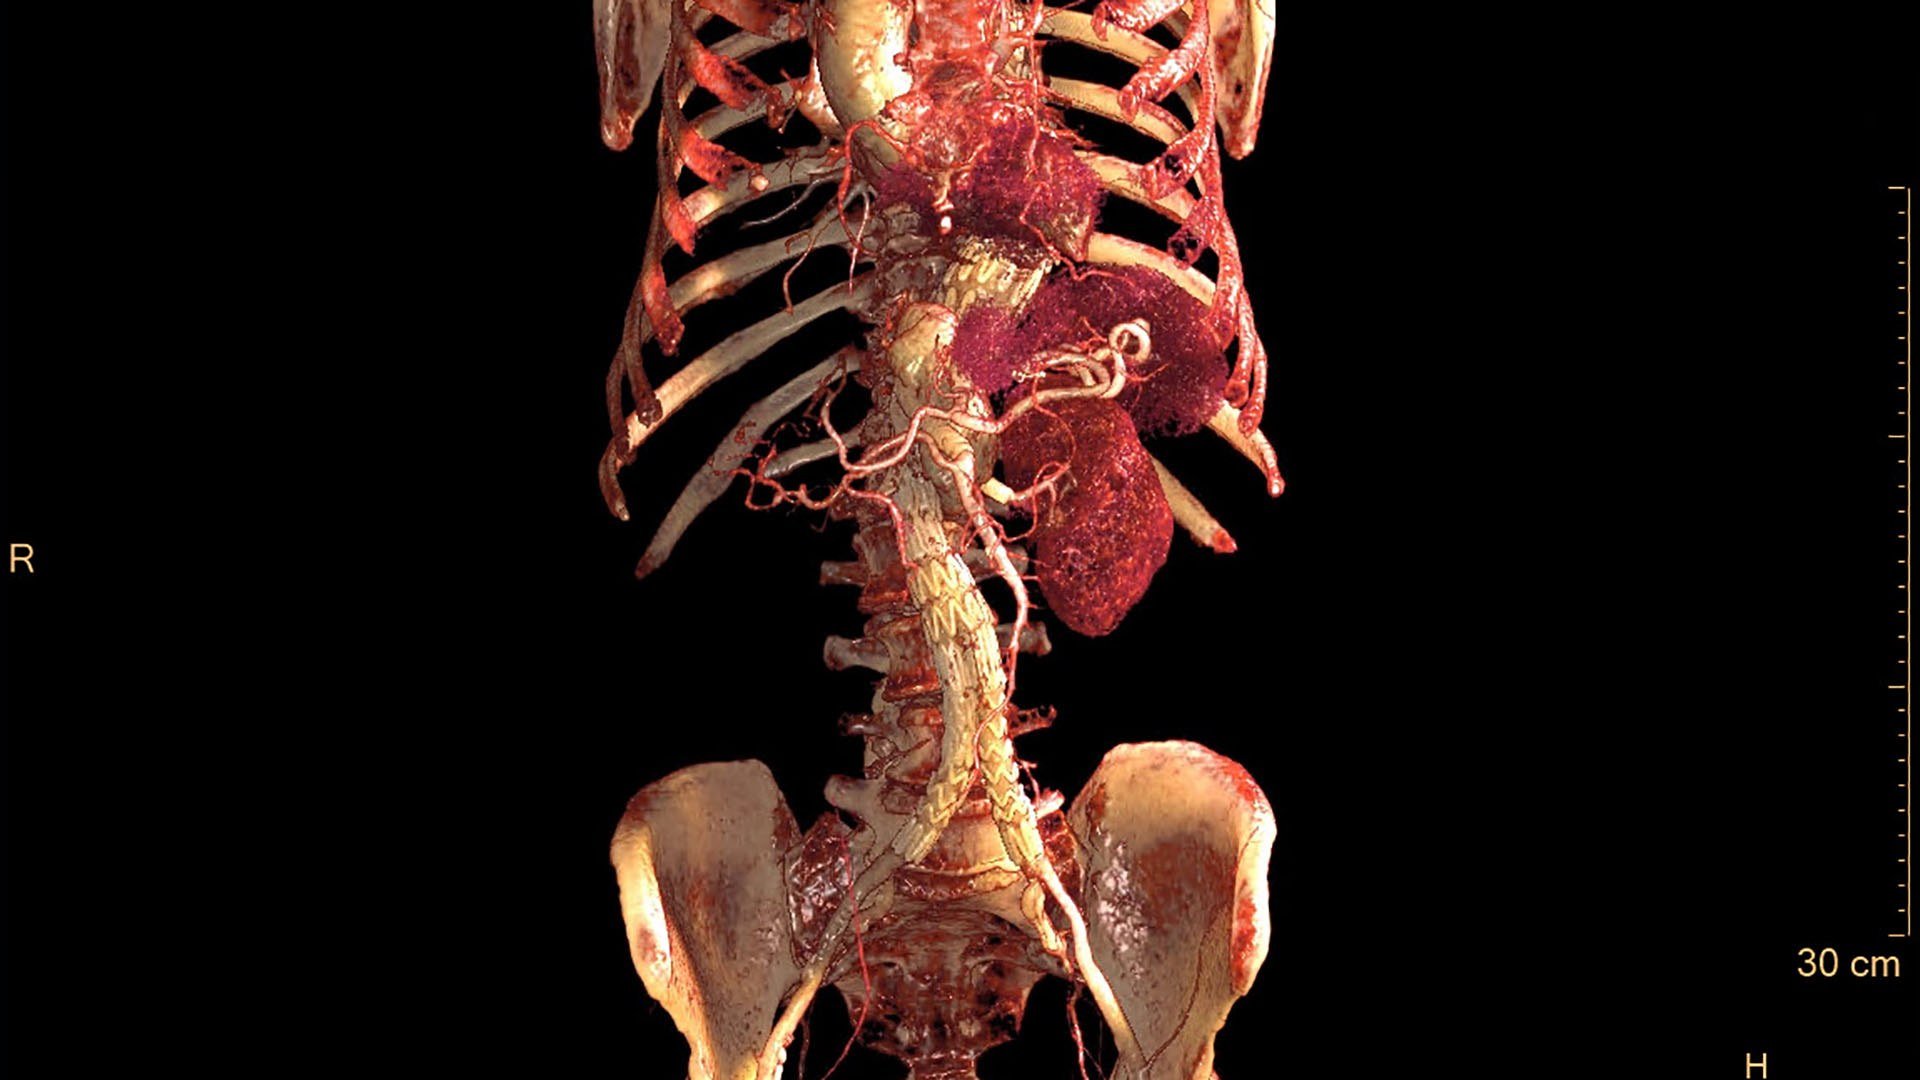

The software also includes a new photorealistic volume rendering [8] technology using an interactive virtual light source to improve the visualization of volumes in terms of their depth and relationship to other key anatomies – enhancing its use as an educational and communication tool.

- IntelliSpace Portal 12 Photorealistic Chest 3D Image

- IntelliSpace Portal 12 Photorealistic Vascular 3D Image